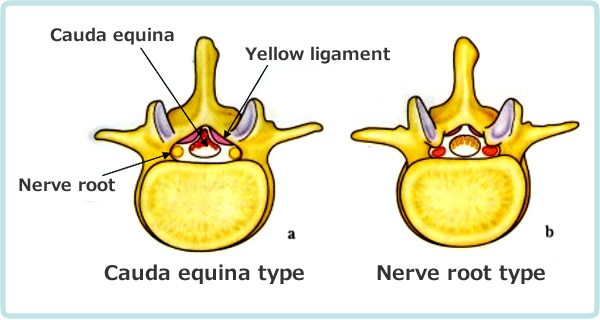

As shown in Fig. 2-1, the lumbar vertebrae have a vertebral foramen, which are connected vertically to form a canal called the spinal canal. The spinal cord is contained in this canal. The spinal cord is then surrounded by the following tissues. In front of the spinal cord, there is an intervertebral disc between the vertebrae, and behind the disc is a longitudinal ligament called the posterior longitudinal ligament. And behind the spinal cord, between the vertebral discs, is the yellow "yellow ligament". The spinal cord is surrounded by the vertebrae, intervertebral discs, posterior longitudinal ligament, and yellow ligament. When these protrude toward the center of the spinal canal due to deformation, herniation injury, or thickening, the spinal canal becomes narrower, putting pressure on the spinal cord causing spinal stenosis.

The mechanism of intermittent claudication is as follows. In scoliosis, the cauda equina nerve, which is located below the second lumbar vertebra. It resembles a horse's tail and is compressed by a deformed yellow ligament or vertebra causing pain and numbness in the lower extremities. The cauda equina nerve has longitudinally distributed blood vessels that supply oxygen and nutrients to the nerve root as shown in Figure 2-2.

Adapted from Kikuchi: Journal of the Japan Orthopedic Association, 62: 571, 1988.

| Type | Cauda equina type | Nerve root type |

|---|---|---|

| Common symptom | Neurogenic intermittent claudication | |

| Subjective symptoms | Abnormal sensation (burning) in lower limbs, buttocks, and perineum | Pain in lower limbs and buttocks |

| Objective findings | Polyradiculopathy | Single-rooted disorder |

Table 2-1 compares the symptoms of the cauda equina type and the nerve root type. The cauda equina type is characterized by bilateral burning sensation due to thickening of the yellow ligament. The nerve root type is pain in the lower extremities and hip region due to unilateral nerve root compression caused by vertebral deformity or herniation. The common symptom is gait disturbance due to symptoms in the lower extremities and hip when walking. The nerve root type is easily cured, but spontaneous healing of the cauda equina type is difficult.